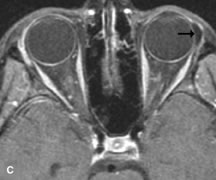

Cystic Lesions

Dermoid cysts appear as rounded, well-defined lesions typically contiguous with an orbital bony suture. The high-intensity signal on T1-weighted images is attributed to the sebaceous-produced lipid contents (Fig. 18).31,50 Mucoceles may demonstrate a hypointense or hyperintense signal on MR images, depending on the concentration of proteinaceous or inflammatory fluid components. The integrity of the bony walls of the expanded sinus cavities cannot be assessed on MR as well as by CT.37,50,55,56 A high-signal intensity on Tl- and T2-weighted images is characteristic of orbital chronic hematic cysts because of the blood-breakdown products within the cysts.57

Fig. 18. A. T1-weighted, (B) T2-weighted fat-suppressed, and (C) T1-weighted fat-suppressed MR scans demonstrate a small dermoid cyst arising near the palpebral portion of the lacrinal gland (arrows). The lesion is similar in signal intensity to fat on the T1-weighted scan (A) consistent with a high adipose tissue content. The lesion shows fat-suppression and low signal intensity on the two fat-suppressed sequences (B and C) confirming its high lipid content.